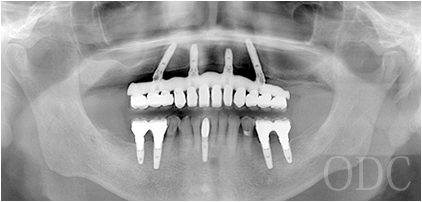

パノラマX線写真

術 後

術前・術後のパノラマX線写真です。上顎(オールオン4)は4本のインプラントにチタンフレームの上部構造が固定されているのがおわかりになると思います。下顎のインプラント埋入部位、上顎のインプラントの本数、再度写真をご覧いただくと、とてもインプラントが埋入されているとわからない程の外観、下顎の残存歯(元々の自分の歯)とも区別がつかない審美性が実現されています。